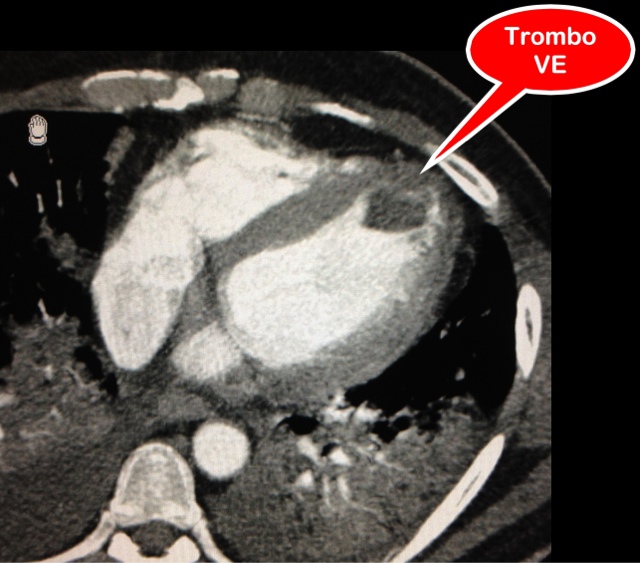

TROMBO ATRIO ESQUERDO

Com o surgimento dos novos aparelhos de tomografia com múltiplas fileiras de detectores e a melhora na resolução temporal e espacial, cada vez mais podemos avaliar o coração e os vasos da base em tomografia de tórax realizadas para suspeitas diagnósticas não cardiológicas, no entanto durante uma avaliação do tórax devemos incluir o coração como parte da rotina radiológica. Neste caso individualizamos uma falha de enchimento hipoatenuante que pode traduzir trombo no interior do átrio esquerdo (auriculeta).